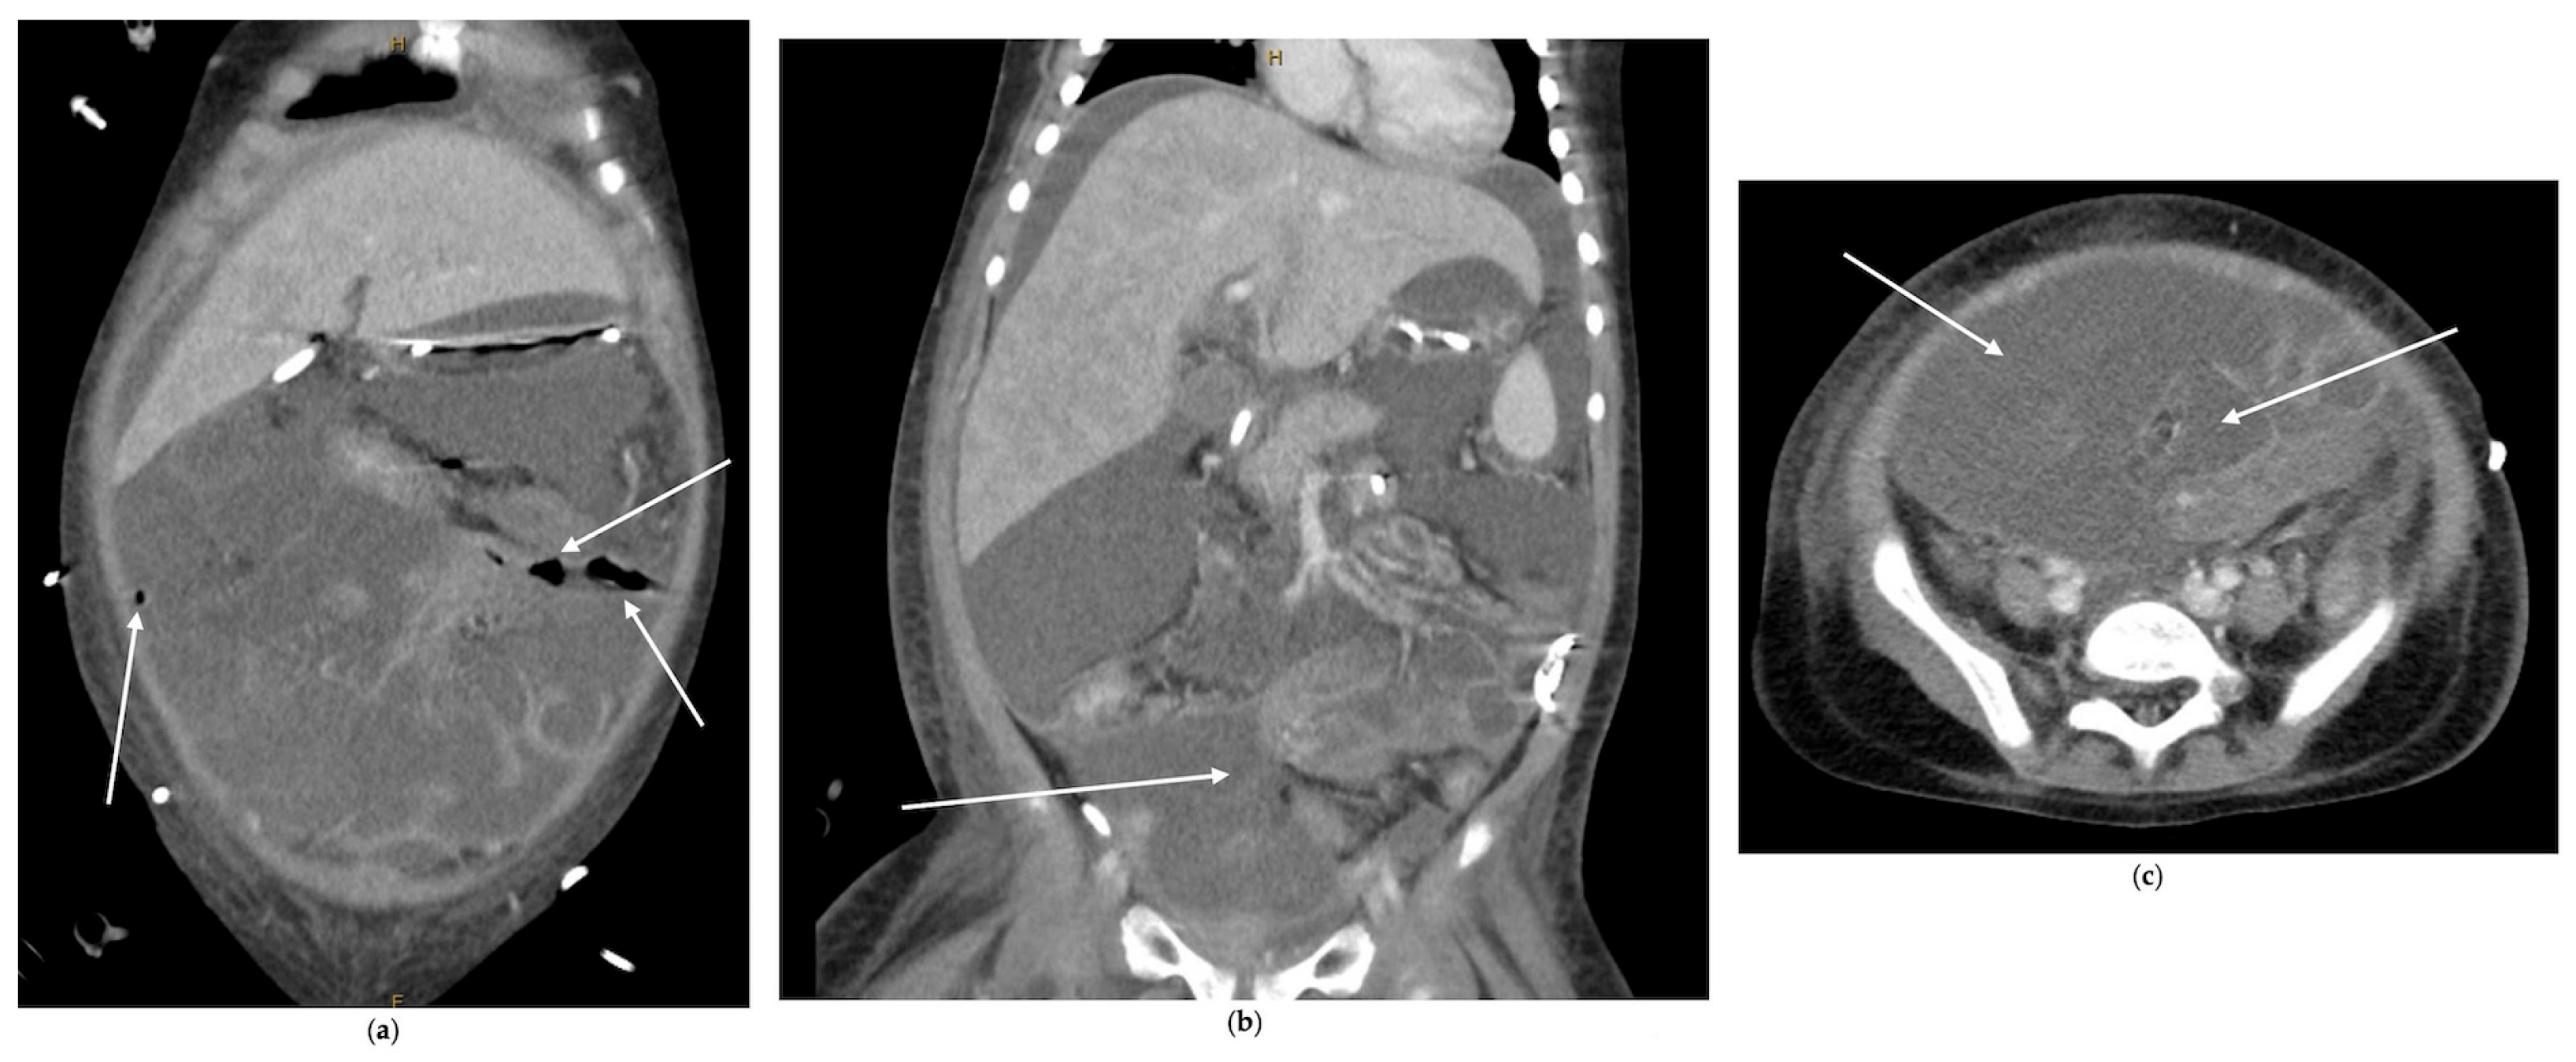

2.1.1. Case 1

2.1.2. Case 2

2.1.3. Case 3

- Incidental imaging clues: Retrospective analysis identified free air in two cases, underscoring that radiographic “soft signs” must be taken seriously in this context.

- Quick and Thorough Imaging: Be ready to order detailed abdominal imaging (such as a CT scan) for any concerning gastrointestinal symptom. A team of specialists should carefully review the images, as subtle signs, such as tiny pockets of air or changes in the bowel wall, can be missed.